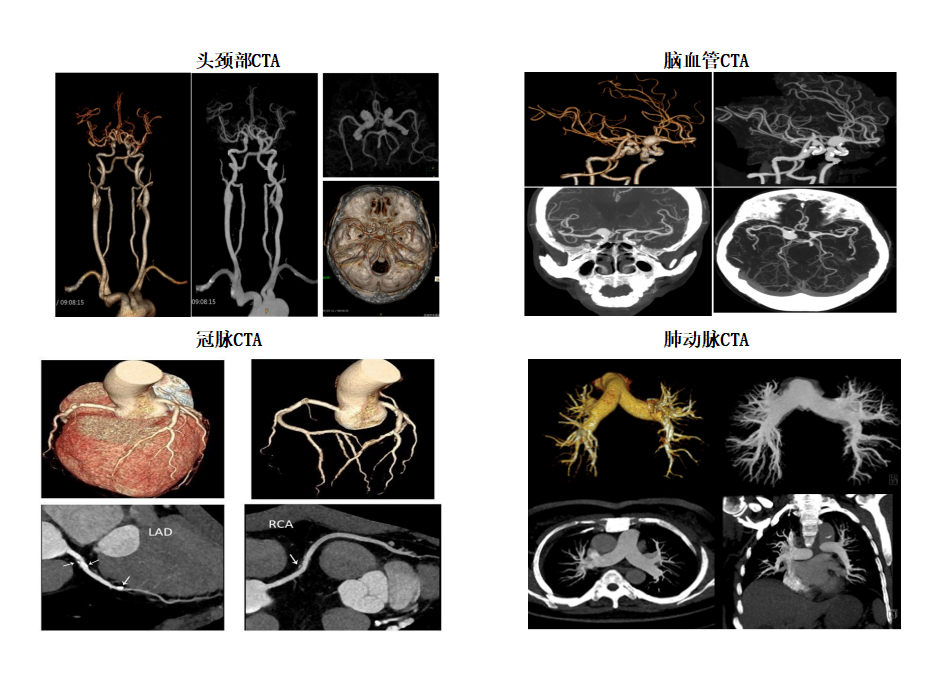

CT血管造影(CTA)检查范围包括冠状动脉、头颈部、肺动脉、主动脉(胸、腹)以及四肢血管造影等。新设备的强大的性能,让本来就很成熟的血管CTA成像与后处理技术更加准确更加便捷。